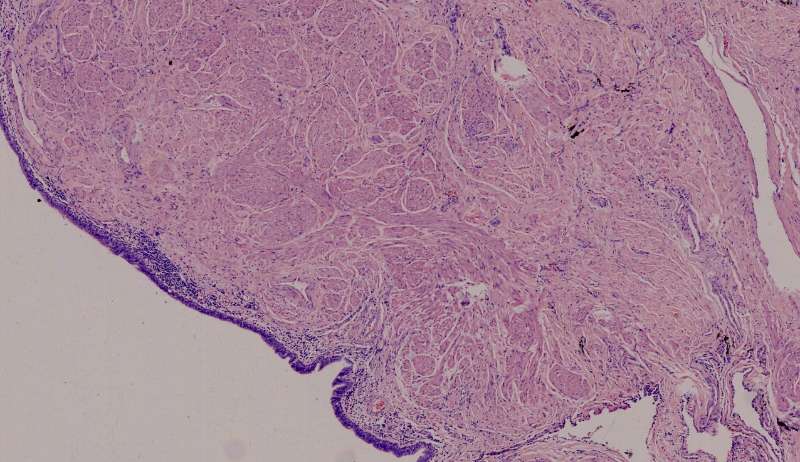

曲霉菌,一条条,呈分支状,分支的角度在45-75°,毛霉菌的分支角度接近直角,今天不讲毛霉菌,我们讲常见病。曲霉菌看上去比较清秀,均匀粗细,一般长在空腔里。

这个人的支气管腔有一大团曲霉,被冲掉了,扩张的支气管有炎症细胞浸润,还有支气管外侧,含铁血黄素沉积。

曲霉菌孢子很少见到,基本都是菌丝团,这里也是支气管扩张区,菌丝团偏黄褐色,也快死了。

支气管扩张都有平滑肌增生吧?王:一般会有 王老师 ,这些是单纯HE染色还是有特殊染色?王:HE